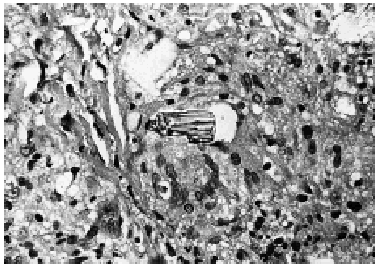

Se realizó una biopsia cutánea de una de las lesiones, cuyo estudio histológico mostró una epidermis normal. Por debajo de ésta, desde la dermis superficial hasta el límite dermo-hipodérmico, se observaba un denso infiltrado granulomatoso constituido por células epitelioides, células gigantes multinucleadas y tipo Langhans, rodeadas por una discreta corona linfocitaria. En el interior de estos granulomas se distinguía un material extraño de color verde amarillento y forma geométrica (figs. 3 y 4).

Fig. 4.--Material extraño dentro de granuloma (hematoxilina-eosina, x 120).